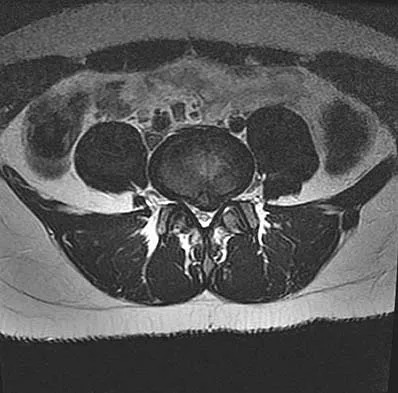

The arrow in the axial T1-weighted MRI scan shown in Figure 18 is pointing to which of the following structures?